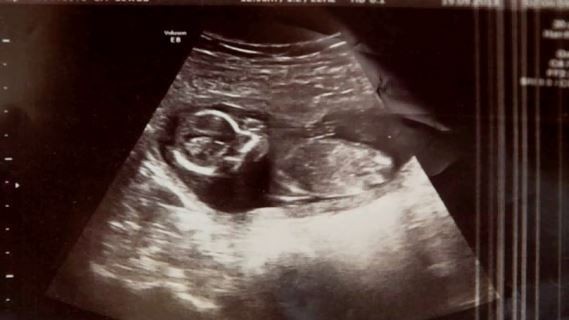

10 dni później, znowu w szpitalu, Michelle miała ostatnie badanie USG przed zabiegiem. Wtedy lekarz odkrył coś szokującego. Podczas badania usłyszał… bicie serca. Mimo poronienia i połknięcia tabletek, kobieta była w ciąży.

Okazało się, że wcześniej spodziewała się bliźniaków i jedno z dzieci zmarło w trakcie poronienia. Nikt nie wie jakim cudem drugie dziecko przeżyło, ale jedno jest pewne. Rodzice są wniebowzięci.